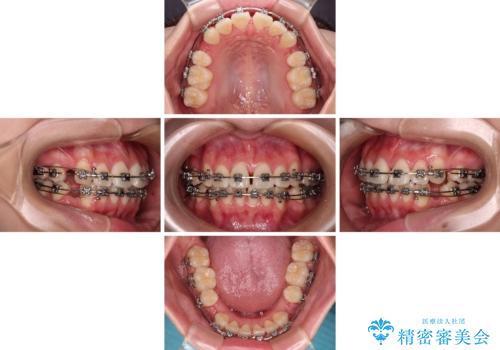

- メタルブラケット

- 1年10ヶ月

- 前歯がくちばしのように飛び出していることを気にして来院された患者様です。

唇が前方に突出している横顔が気になっているため、上下左右の第一小臼歯4本を抜歯し、ワイヤー装置にて矯正治療を行うこととしました。